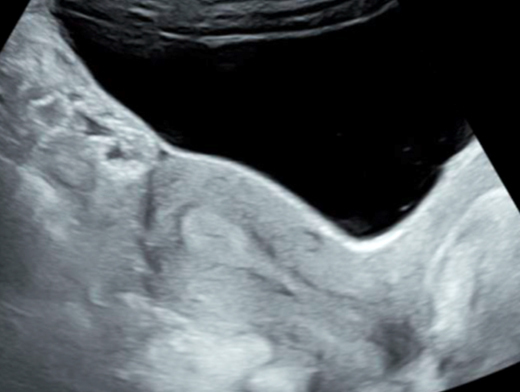

Figure 1 (Rodolphe Matias de Sousa, La Revue du Praticien) Cette image échographique d’un hématome rétro-placentaire typique met en évidence : – une collection hypoéchogène ou anéchogène entre le placenta et l’utérus ; – un épaississement du myomètre sous-jacent, parfois hyperéchogène si un caillot s’est formé ; – un décollement placentaire partiel ou total selon la sévérité ; – une absence ou diminution du flux sanguin au Doppler dans la zone de l’hématome. Les premiers résultats du bilan biologique prescrit à l’arrivée de Mme G. objectivent : hémoglobine = 11 g/dL ; plaquettes = 100 G/L ; taux de prothrombine (TP) = 92 % ; temps de céphaline activée (TCA) = 1,10 ; fibrinogène = 2 g/L ; aspartate aminotransférase (ASAT) = 26 UI/L ; alanine aminotransférase (ALAT) = 24 UI. La pression artérielle de Mme G. est à 165/95 mmHg et sa fréquence cardiaque à 110 bpm.

Mme G. est finalement césarisée sous anesthésie générale sans complication. Lors de l’hystérotomie, le liquide amniotique est sanglant avec de nombreux caillots. Les pertes sanguines sont estimées à 1 500 mL. L’équipe d’anesthésie a administré en peropératoire un culot de globules rouges et un plasma frais congelé (PFC), ainsi que de l’acide tranexamique. L’utérus est tonique en fin d’intervention. Au cours de la surveillance en salle de surveillance post-interventionnelle (SSPI), à quatre heures postopératoires, Mme G. a une barre épigastrique résistante aux antalgiques de palier 3. Les constantes sont les suivantes : pression artérielle = 190/110 mmHg ; fréquence cardiaque = 120 bpm ; saturation en oxygène = 99 % en air ambiant. Compte tenu de la tachycardie, vous réalisez une échographie transabdominale dont les images sont les suivantes. Figure 2a (Rodolphe Matias de Sousa, La Revue du Praticien)Figure 2b (Rodolphe Matias de Sousa, La Revue du Praticien)Figure 2c (Rodolphe Matias de Sousa, La Revue du Praticien) Vous décidez d’avancer le prochain bilan biologique et récupérez les résultats suivants : hémoglobine = 8,7 g/dL ; plaquettes = 40 G/L ; TP = 65 % ; TCA = 1,02 ; fibrinogène = 2 g/L ; haptoglobine indosable ; ASAT = 260 UI/L ; ALAT = 240 UI/L.